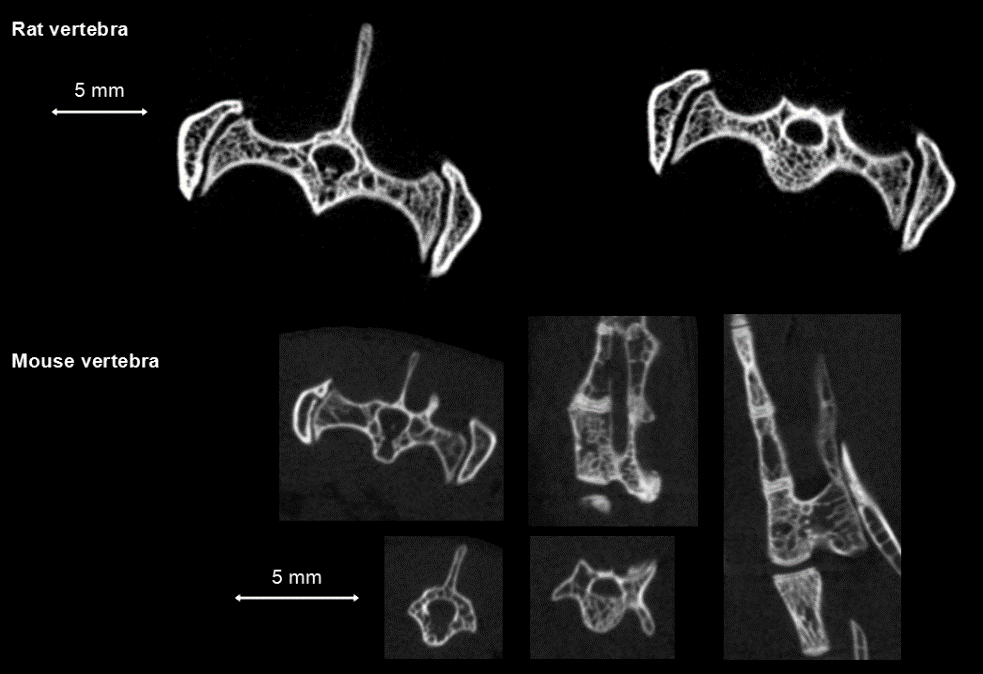

In vivo measurement of spinal vertebrae in rats: high definition ring acquisition, acquisition time: 4min, FDK reconstruction, 50 and 20μm voxel size.

脊椎骨測量.png

Bone data processing with PMOD software: By selecting the region of interest (ROI) on the CT scan image for threshold segmentation and other operations, cortical bone (bone dense) and bone trabeculae (bone cancellous) can be segmulated and extracted into different tissue regions respectively, so as to study and analyze various morphological characteristics of them.

骨骼分析.png